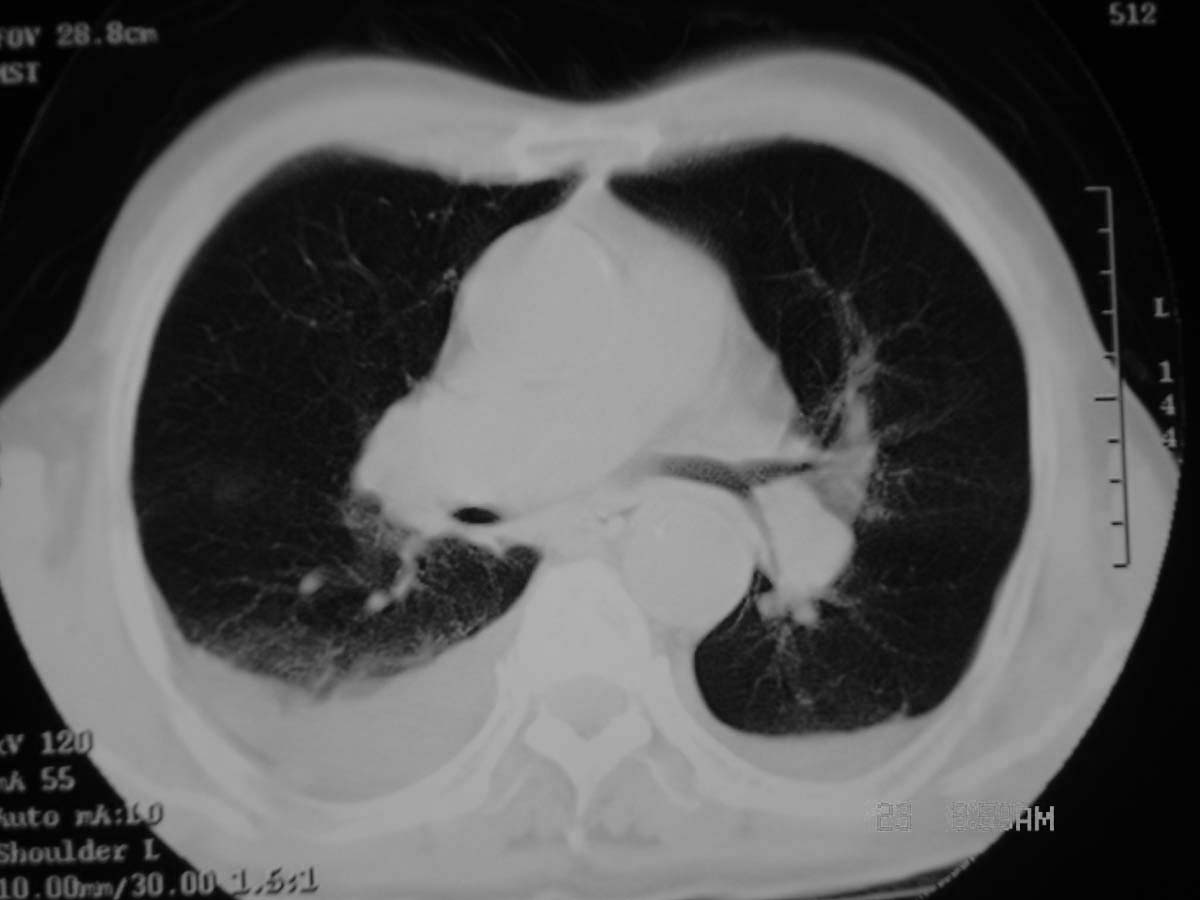

以下是引用守望可可西里在2006-11-23 14:33:00的发言:[br][br] 糖尿病病人很容易继发结核,病人又有双侧胸膜增厚、粘连、胸腔积液以及双上肺的斑片状、条索状影结核病灶影,以一元论考虑,右下肺病变首先考虑干酪性肺炎,可以正规抗炎治疗后复查,排除一般的肺炎。